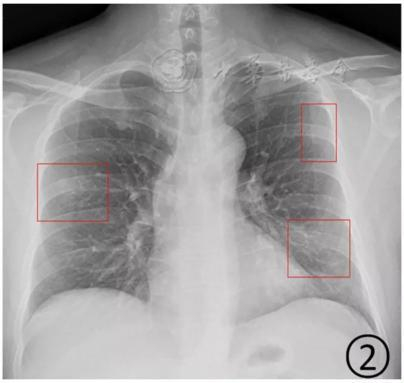

根据感染程度不同,有的仅单侧肺出现这种磨玻璃影,还有的双侧都有。磨玻璃影可以累及一个肺叶,也可同时累及多个肺叶。

▲上面的图:单侧肺出现磨玻璃影,累及一个肺叶; ▲下面的图:双侧肺均出现磨玻璃影,累及多个肺叶(图片来自网络)

按照国家卫健委发布的新型冠状病毒肺炎试行第六版诊疗方案之中的临床分型,新冠肺炎分为轻型、普通型、重型及危重型。在患者的肺部CT中,轻型者没有比较明显的肺炎改变;普通型者以肺部出现局限性斑片状或很多节段性片状“病灶”为主(图②);重型者双肺可出现较多的白色小斑片“病灶”,部分融合成大片状“病灶”(图③);危重型者会有“白肺”表现(图④)。